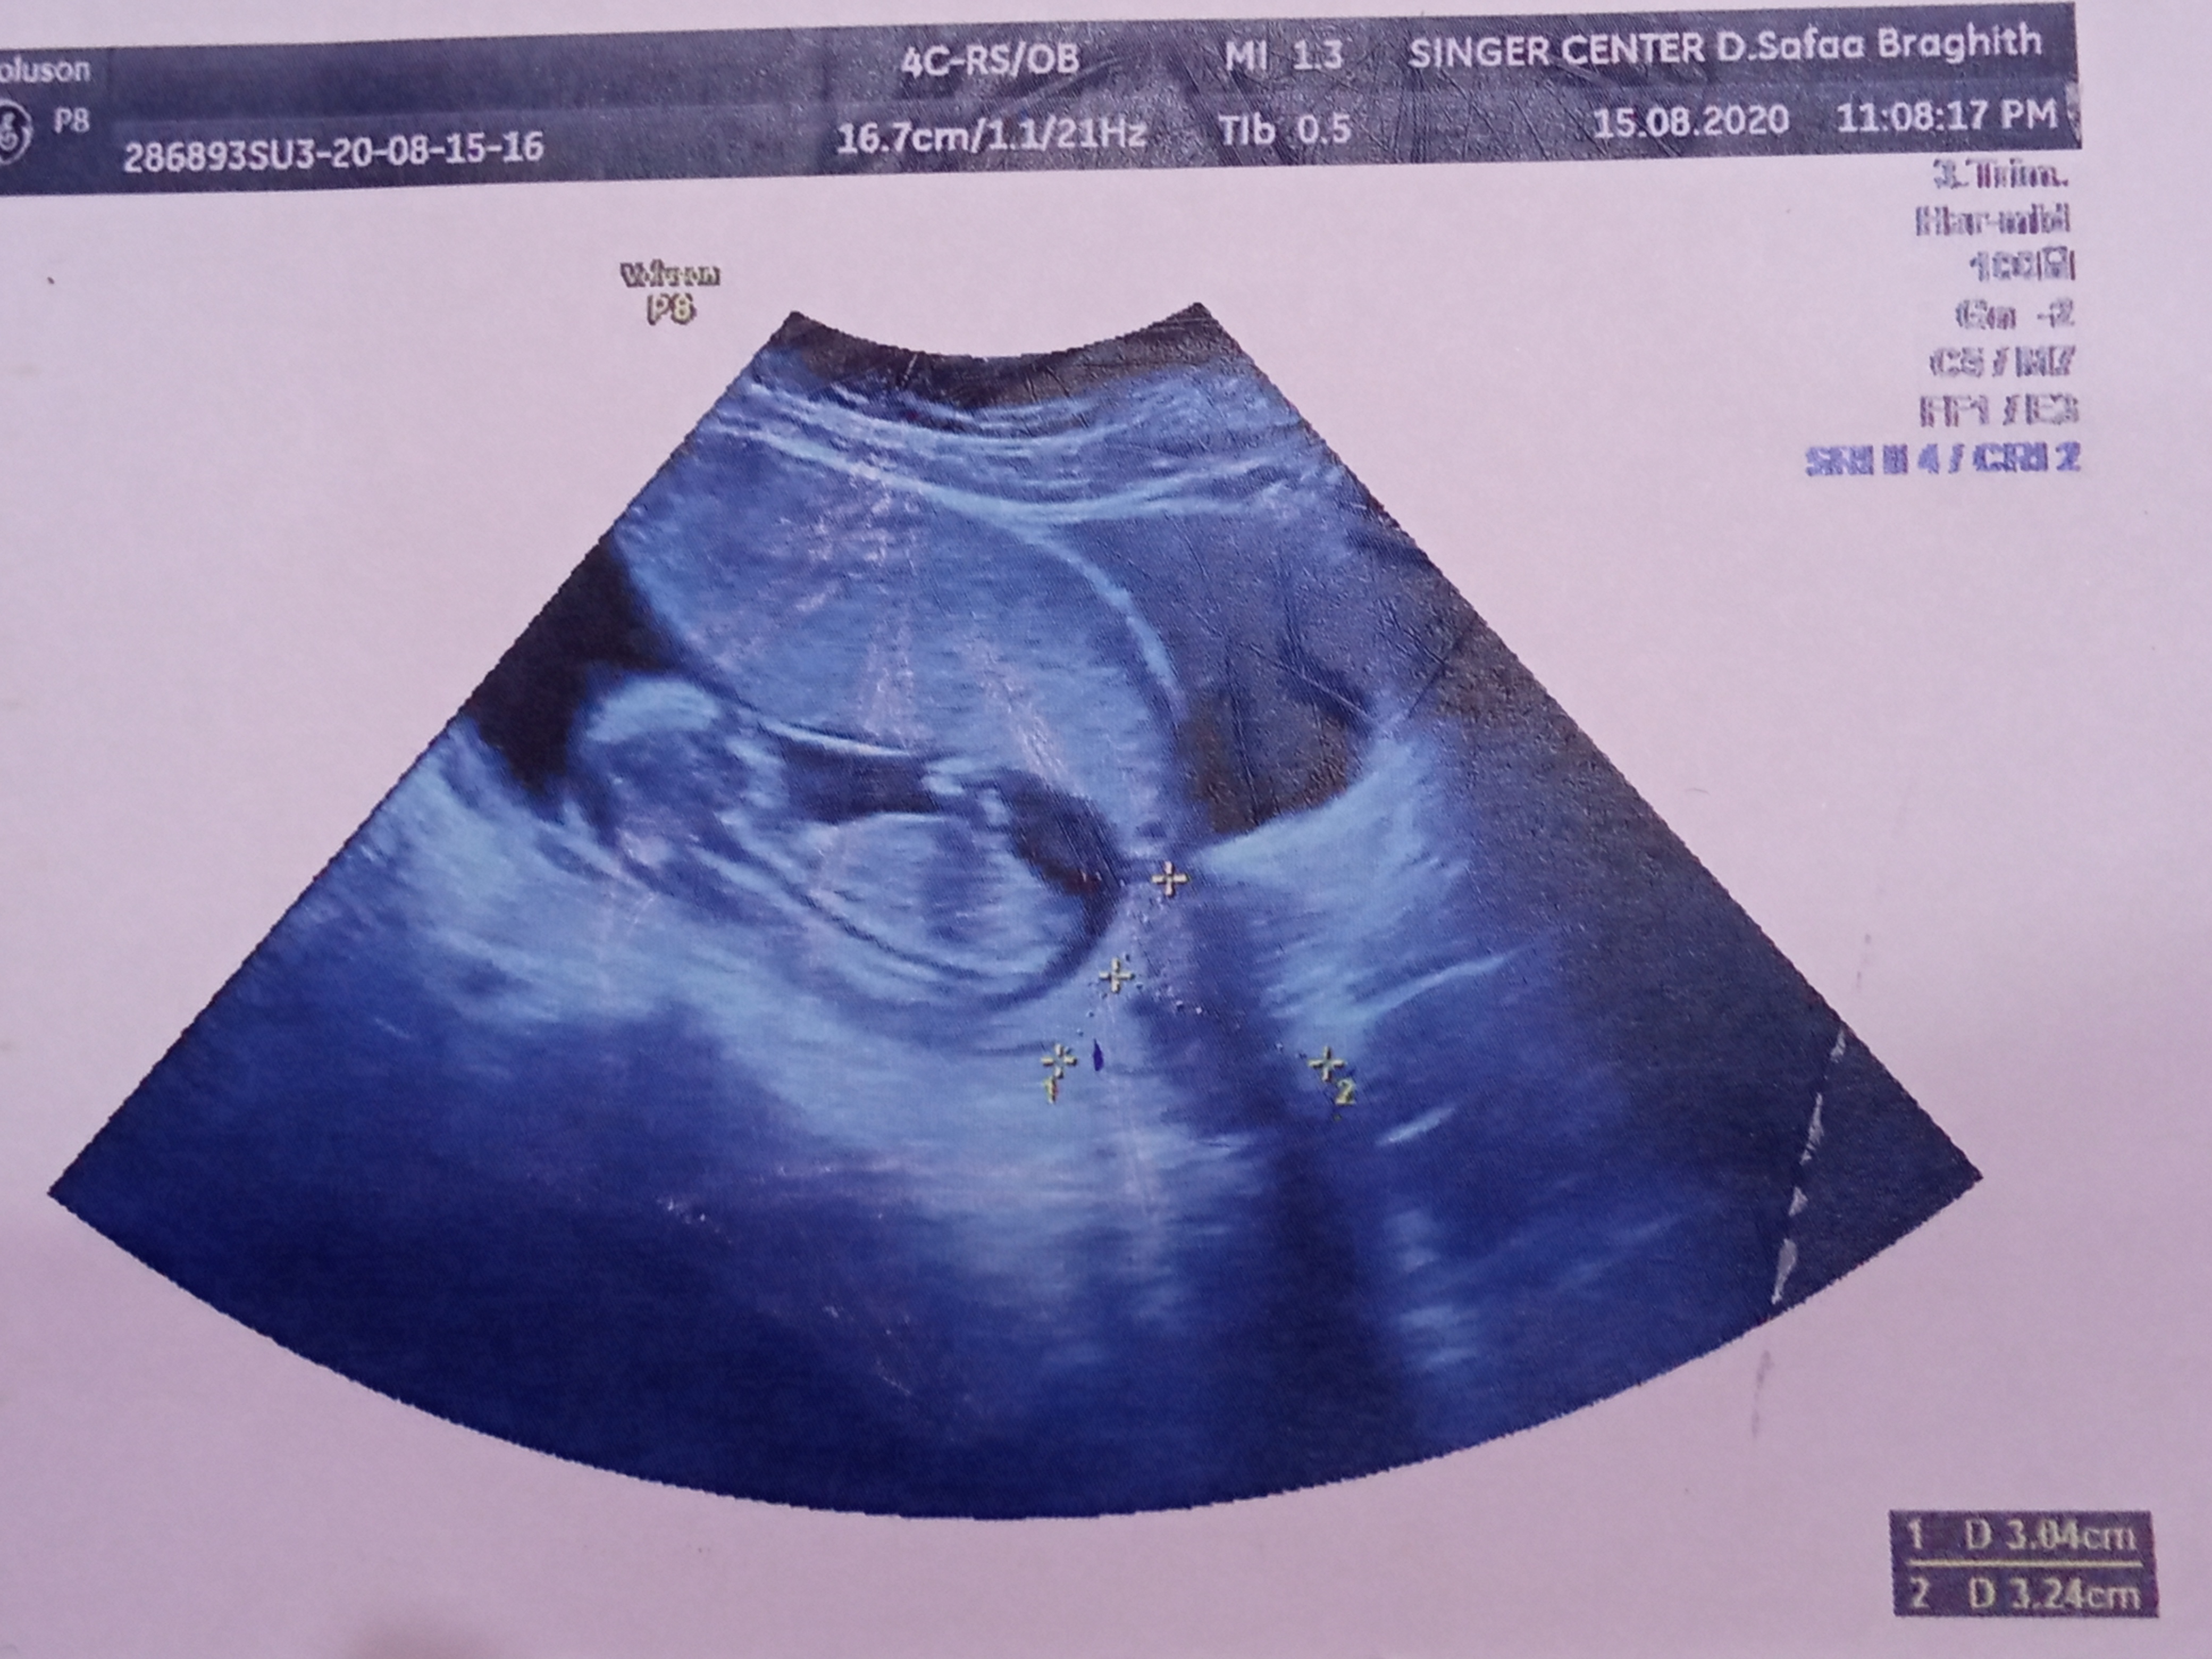

انا سويت سونار وابغى اعرف كم طول عنق الرحم؟ وهل يحتاج ربط او لا ؟ انا حامل في الاسبوع 21